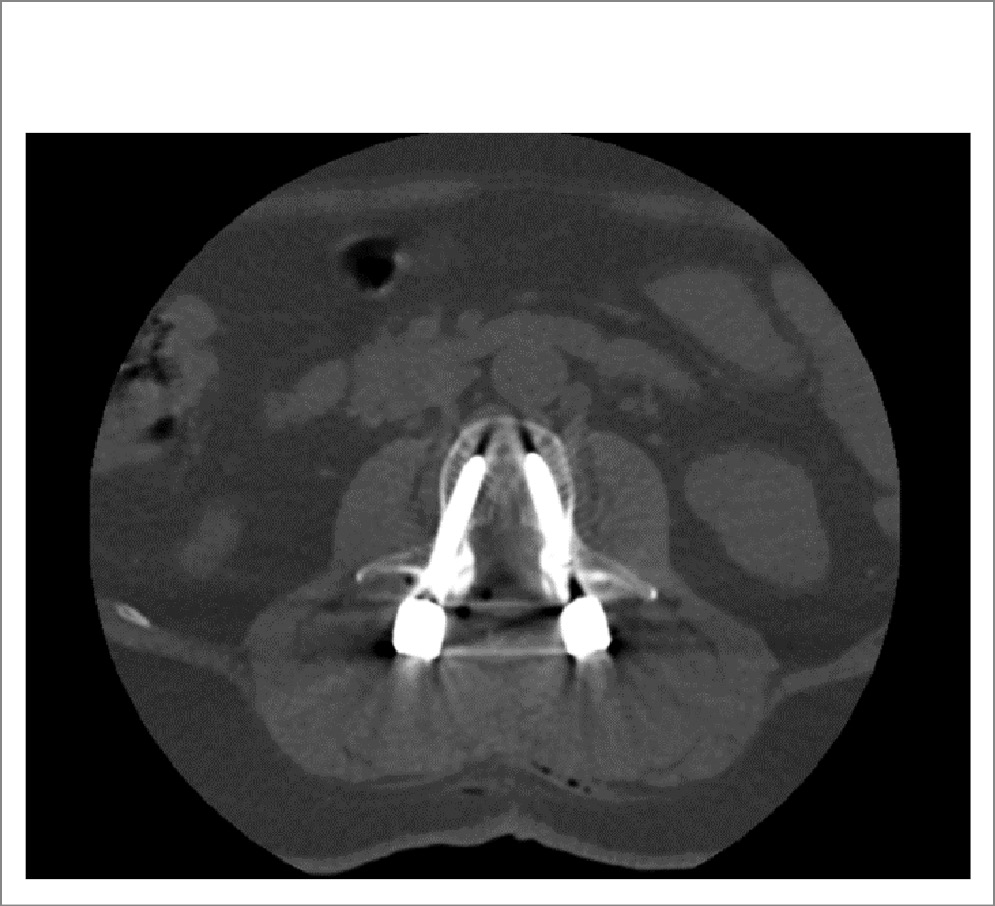

Произведены задний транспедикулярный спондилодез LII–LIII–LIV путем установки транспедикулярных металлофиксаторов (рис. 2), декомпрессивная ламинэктомия LIII (рис. 3), аркотомия LII и LIV c резекцией гипертрофированной желтой связки, медиальной фасетотомии гипертрофированных суставов. Корешки и ДМ декомпремированы. Эпидуральное пространство выше и ниже зоны ламинэктомии проходимо.

Рис. 3. Аксиальная проекция на уровне LIII позвонка, ламинэктомия и транспедикулярная винтовая фиксация.

Таким образом, в приведенном клиническом случае у пациентки отмечали смешанный ПС по данным нейровизуализации (сагиттальный размер ДМ на уровне LIII–LIV – 0,6 см, сужение латеральных карманов, больше слева). Учитывая полифакторность дегенеративного стеноза (билатеральную сублигаментарную экструзию, гипертрофию желтых связок, гипертрофию фасеточных суставов, лестничный антелистез тел LIII, LIV), боль в ПО позвоночника и НПХ, а также отсутствие эффекта от КЛ, принято решение о проведении декомпрессии на уровне стеноза с установкой транспедикулярных металлофиксаторов LII–LIII–LIV.